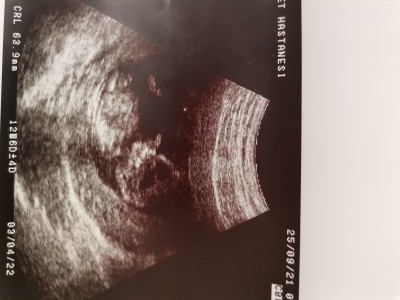

Kızlar cinsiyet tahmini yapabilir misiniz :)

Cinsiyet tahmini 12 haftalık

12 haftalık

Kız gibi geldi :)

Cikinti içe doğru genelde kız böyle oluyo :)) bence kız öğrenirseniz bana da yazın

Erkek gibi geldi

Nuba göre kız gibi ama çok anlamadım

Erkek bence cinsiyet organini göremedim ama kafası aynı benm oğlan. Ben kime söylesem hep doğru çıkmıştır. Tabiki doktordan iyi bilemeyiz ama :) gönlünüzdeki neyse o olsun

Erkek gibi geldi bana da çünkü ayaklar yukarda gördüğüm kadarıyla :)

Banada erkek gibi geldi

Erkek gibi sanki:)

Kız benziyor konum olarak